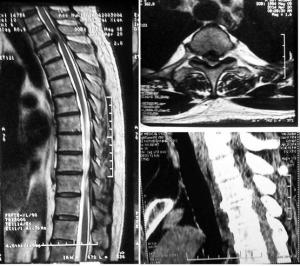

首例胸椎间盘突出症是由Middiefon于1911年在尸体上发现的胸椎间盘突出症在临床上虽不是多见,但其发病率在不同学者的报道中差异甚大,约占脊柱椎间盘突出症总例数的0.12%~1.5%不等患者多为40岁左右的中年人,男女比例相近据文献报道胸椎间盘突出的病例有75%发生在胸8以下。胸4水平以上的胸椎间盘突出症被视为个案曾在医学文献上有过报告。要对疾病有一个较全面的了解和掌握,不仅要采取恰当的疗法,还要指导病人进行正确的康复锻炼,尤其是要让其放下思想包袱,主动使用赵氏养生腰椎贴调理,才能够取得良好的效果。